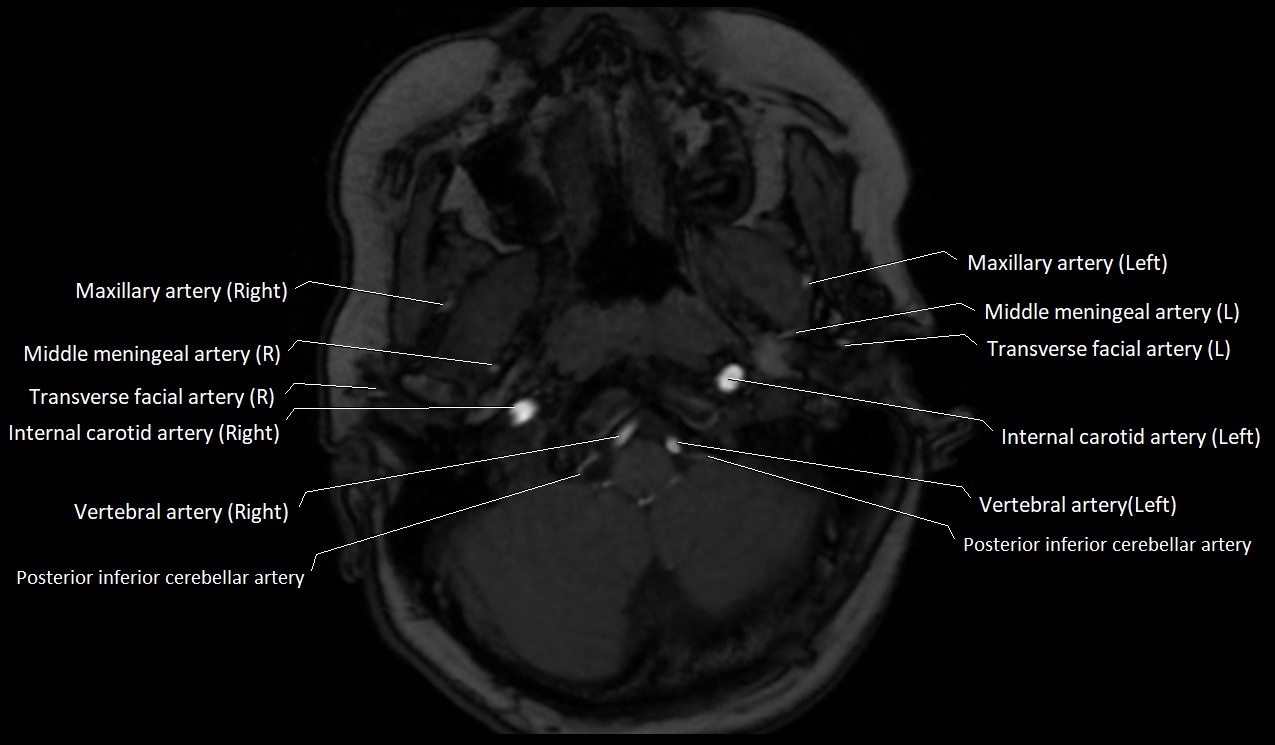

MRI images

image